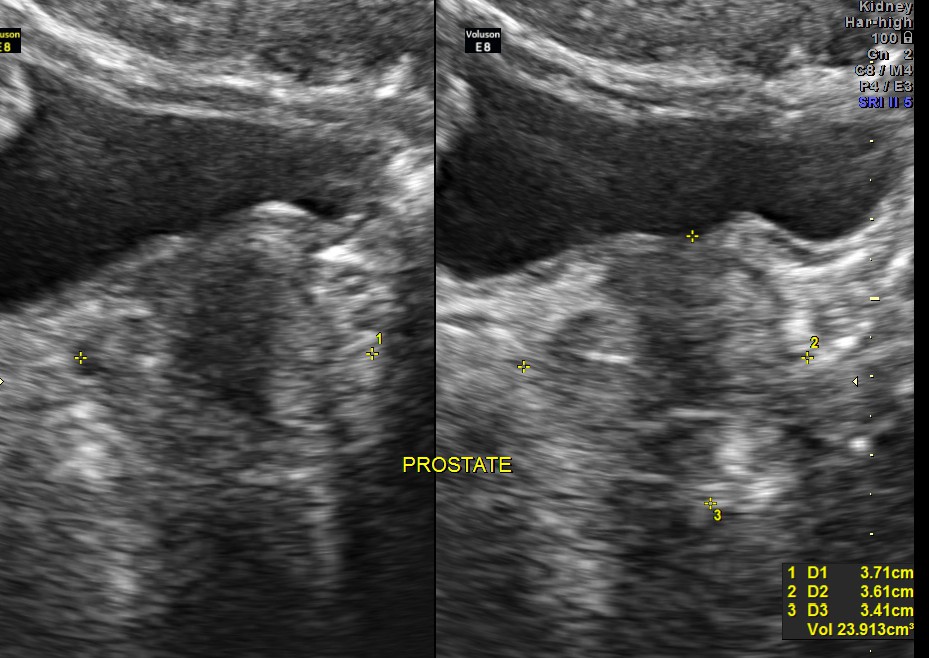

The scan was otherwise normal.